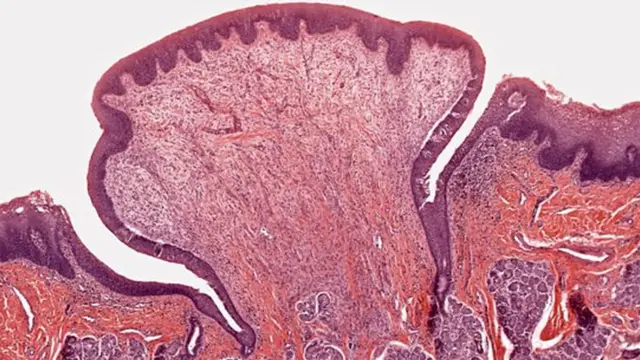

- 8 semanas de gestación

Tus receptores del gusto y el olfato se conectaron al cerebro.

En este punto, eras un feto del tamaño de una uva.

Tu rostro se estaba empezando a formar, así como algunas de las estructuras necesarias para saborear y olfatear.

En el lugar en el que ahora está tu lengua emergieron células gustativas diminutas.

Eran las que se desarrollarían de manera que pudieras detectar los cinco sabores principales.

Racimos de unas 50 a 100 de estas diminutas células se convertirían en papilas, y ya hay nervios conectándolas a "centros de sabor" en ciernes, en los que tu cerebro ahora reconoce los sabores.

Al mismo tiempo, tus receptores olfativos estaban apareciendo en tu nariz, que -en ese momento al menos- era miniatura, y estos también se conectaron a la parte de tu cerebro que procesa los diferentes olores.